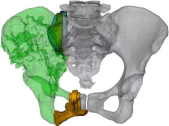

3D打印假体设计

据主刀医师徐生林介绍,本例病例将整个右侧半骨盆Ⅰ+Ⅱ+Ⅲ+Ⅳ区(累及骶骨)进行整块切除,同时切除肿瘤覆盖的部分骶骨。3D打印假体所有骨接触界面均设计为骨整合结构,有利于骨长入和骨盆假体的永久稳定。耻、坐骨结构不规则,因此设计组配式结构,有利于术中操作,极大地方便了术中的假体安装。

3D打印技术的出现,使骨肿瘤的精准切除成为了可能,3D打印制造技术能够很好地适形匹配肿瘤切除后的骨结构,通过假体-骨接触面的特殊制造技术达到假体-骨整合,解决了骨肿瘤切除后大段骨关节缺损的重建问题,在生物力学重建和功能重建上比常规假体优势明显。3D打印假体使骨肿瘤切除重建进入“个性化、精准化、私人定制”时代。